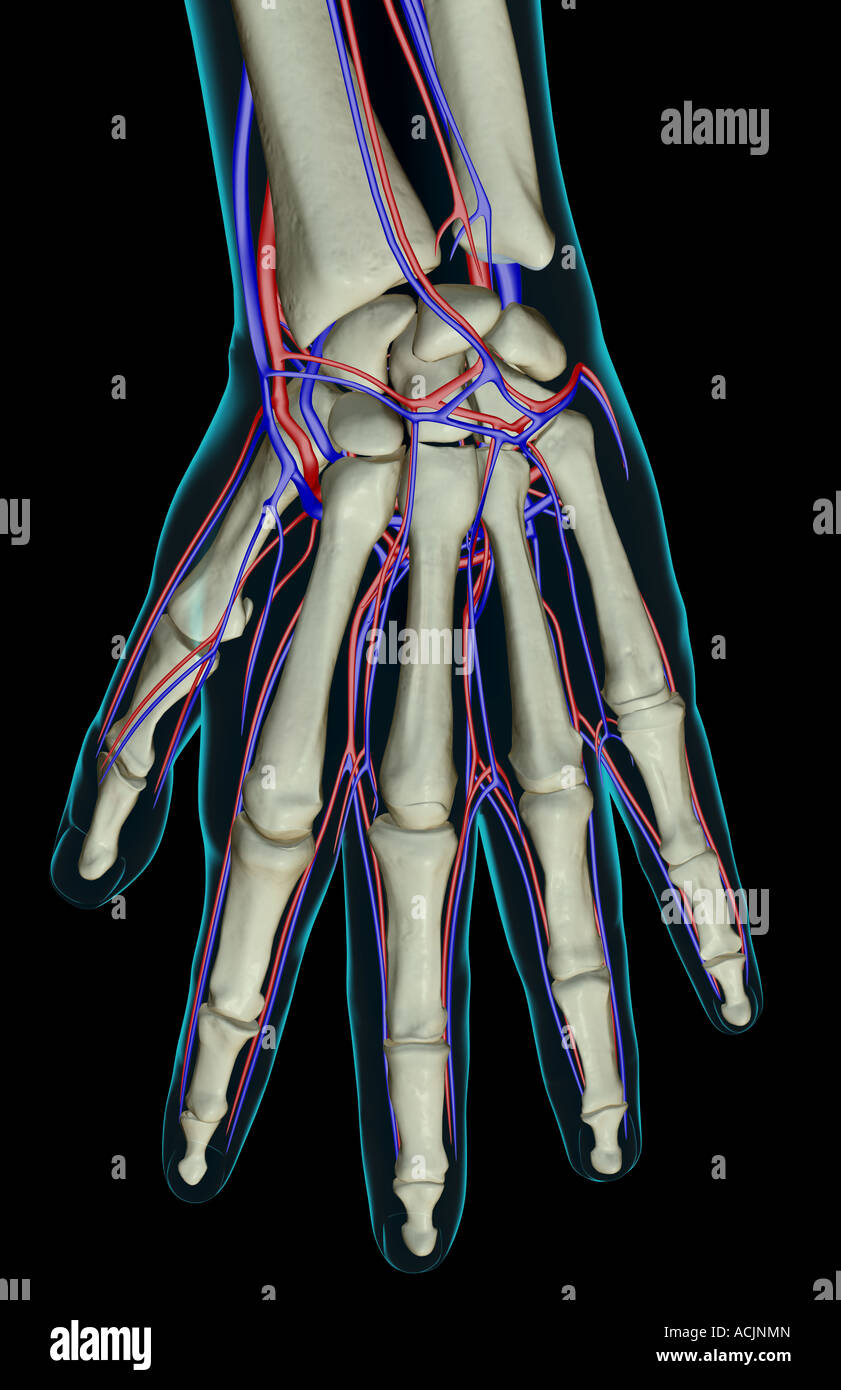

The blood supply of the hand Stock Photohttps://www.alamy.com/image-license-details/?v=1https://www.alamy.com/stock-photo-the-blood-supply-of-the-hand-13172228.html

The blood supply of the hand Stock Photohttps://www.alamy.com/image-license-details/?v=1https://www.alamy.com/stock-photo-the-blood-supply-of-the-hand-13172228.htmlRFACJNMN–The blood supply of the hand